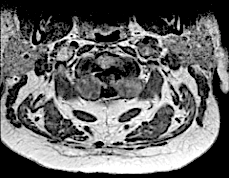

Corte axial C2